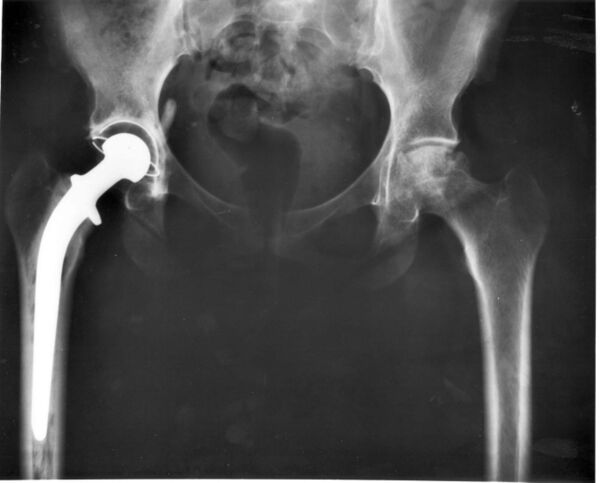

Эндопротезирование тазобедренного сустава — хирургическая операция, при которой тазобедренный сустав заменяется протезным имплантатом, то есть протезом тазобедренного сустава.

Такая операция по замене сустава обычно проводится для облегчения боли при артрите или при некоторых переломах бедра. Полное эндопротезирование тазобедренного сустава состоит из замены как вертлужной впадины, так и головки бедренной кости, в то время как гемиартропластика обычно заменяет только головку бедра[1].

При ТЭТБС заменяется проксимальный отдел бедра и вертлужная впадина. Пораженные участки сустава заменяются на эндопротез, повторяющий анатомическую форму здорового сустава и позволяющий выполнять необходимый объем движений.

В вертлужную впадину имплантируется ацетабулярная чашка. В чашку устанавливается полиэтиленовый или керамический вкладыш. В бедро имплантируется ножка с конусом на шейке для крепления головки эндопротеза.